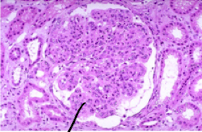

Name the pathology that is shown in the glomerulus below:

Amyloidosis